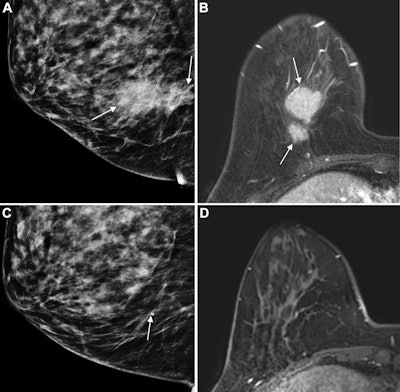

Images of the right breast in a 63-year-old woman with estrogen receptor–low, HER2–positive breast cancer. (A) Mediolateral oblique mammogram obtained before neoadjuvant chemotherapy shows a 5-cm, irregular, spiculated, hyperdense mass (arrows) without calcification in the lower central breast. (B) Axial contrast-enhanced T1-weighted MRI scan obtained before chemotherapy shows two abutting malignant masses (arrows) in the lower central breast. (C) Mediolateral oblique mammogram after chemotherapy shows a decrease in tumor size, with only a biopsy marker (arrow) at the corresponding site. (D) Axial contrast-enhanced T1-weighted MRI scan after chemotherapy shows no residual enhancement in the tumor bed. This radiologic complete response corresponded with pathologic complete response, as determined via pathologic examination after breast-conserving surgery.RSNA